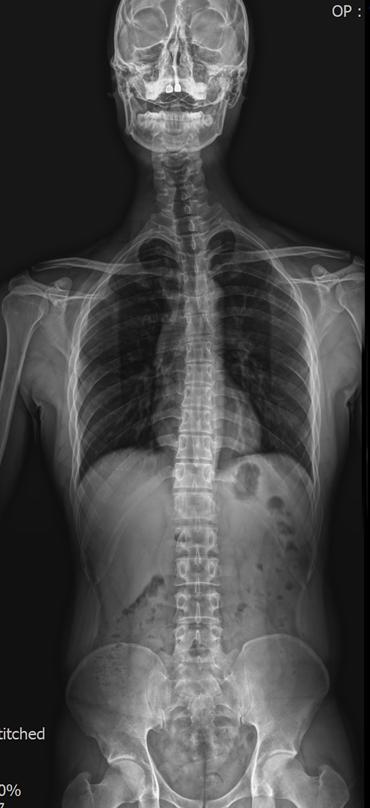

Manual therapy can improve posture and spinal balance. A clinical example of reverse cervical curve correction. Reverse Curve Correction Case

Reverse Curve Correction Case Read Post »

Reverse cervical curve can cause chronic neck pain. Learn how manual therapy helps restore spinal alignment. Correcting Reverse Cervical Curve

Correcting Reverse Cervical Curve Read Post »